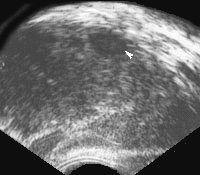

Магнитно-резонансная томография (МРТ), а также рентгеновская компьютерная томография – высокочувствительные методы визуализации, применяемые в качестве дополнительных методов диагностики.Диагностика рака предстательной железы на ранних стадиях развития возможно только при профилактическом обследовании, либо случайно после проведения трансуретральной резекции по поводу аденомы простаты. В связи с этим, мужчинам в возрасте после 40 лет рекомендуется проходить обследование у уролога как минимум 1 раз в год с обязательным определение уровня ПСА, проведением пальцевого ректального исследования, и трансректальной ультразвуковой диагностики (ТРУЗИ).